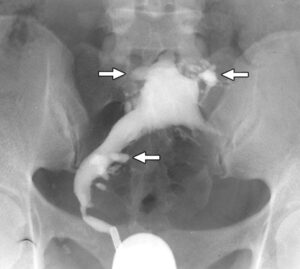

٭ رحم کا الٹراساؤنڈ

٭ رحم کا ایم آر آئی

٭ پیلوک امیجنگ (الٹراساؤنڈ/ ایم آر آئی) ایڈینو مائیوسس کے آثار کی نشاندہی کر سکتی ہیں۔ تاہم اس کی تصدیق کا واحد طریقہ یہ ہے کہ ہسٹریکٹومی (بچہ دانی نکالنے) کے بعد رحم کا معائنہ کیا جائے۔